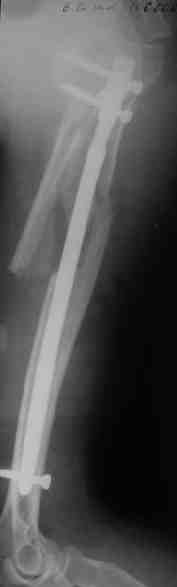

Re: Оскольчатый перелом плеча

послал Maxim Agalakov 20 Август 2006, 22:34

Прооперировали больную с переломом плеча все же гвоздем, Фото в приложении.